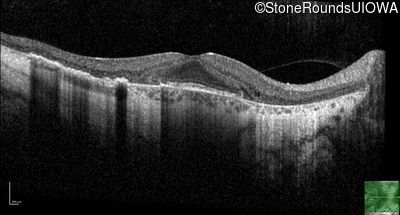

Age at visit: 35 years

This 35-year-old man has trouble in low light and when moving around in busy places. He first reported trouble seeing in low light at age 13. His maternal grandfather was similarly affected.